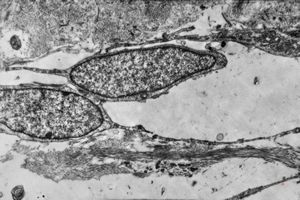

F,68y. | APUD carcinoma

F,68y. | APUD carcinoma

F,68y. | APUD carcinoma

F,68y. | APUD carcinoma

F,68y. | APUD carcinoma (Bodian siver impregnation)